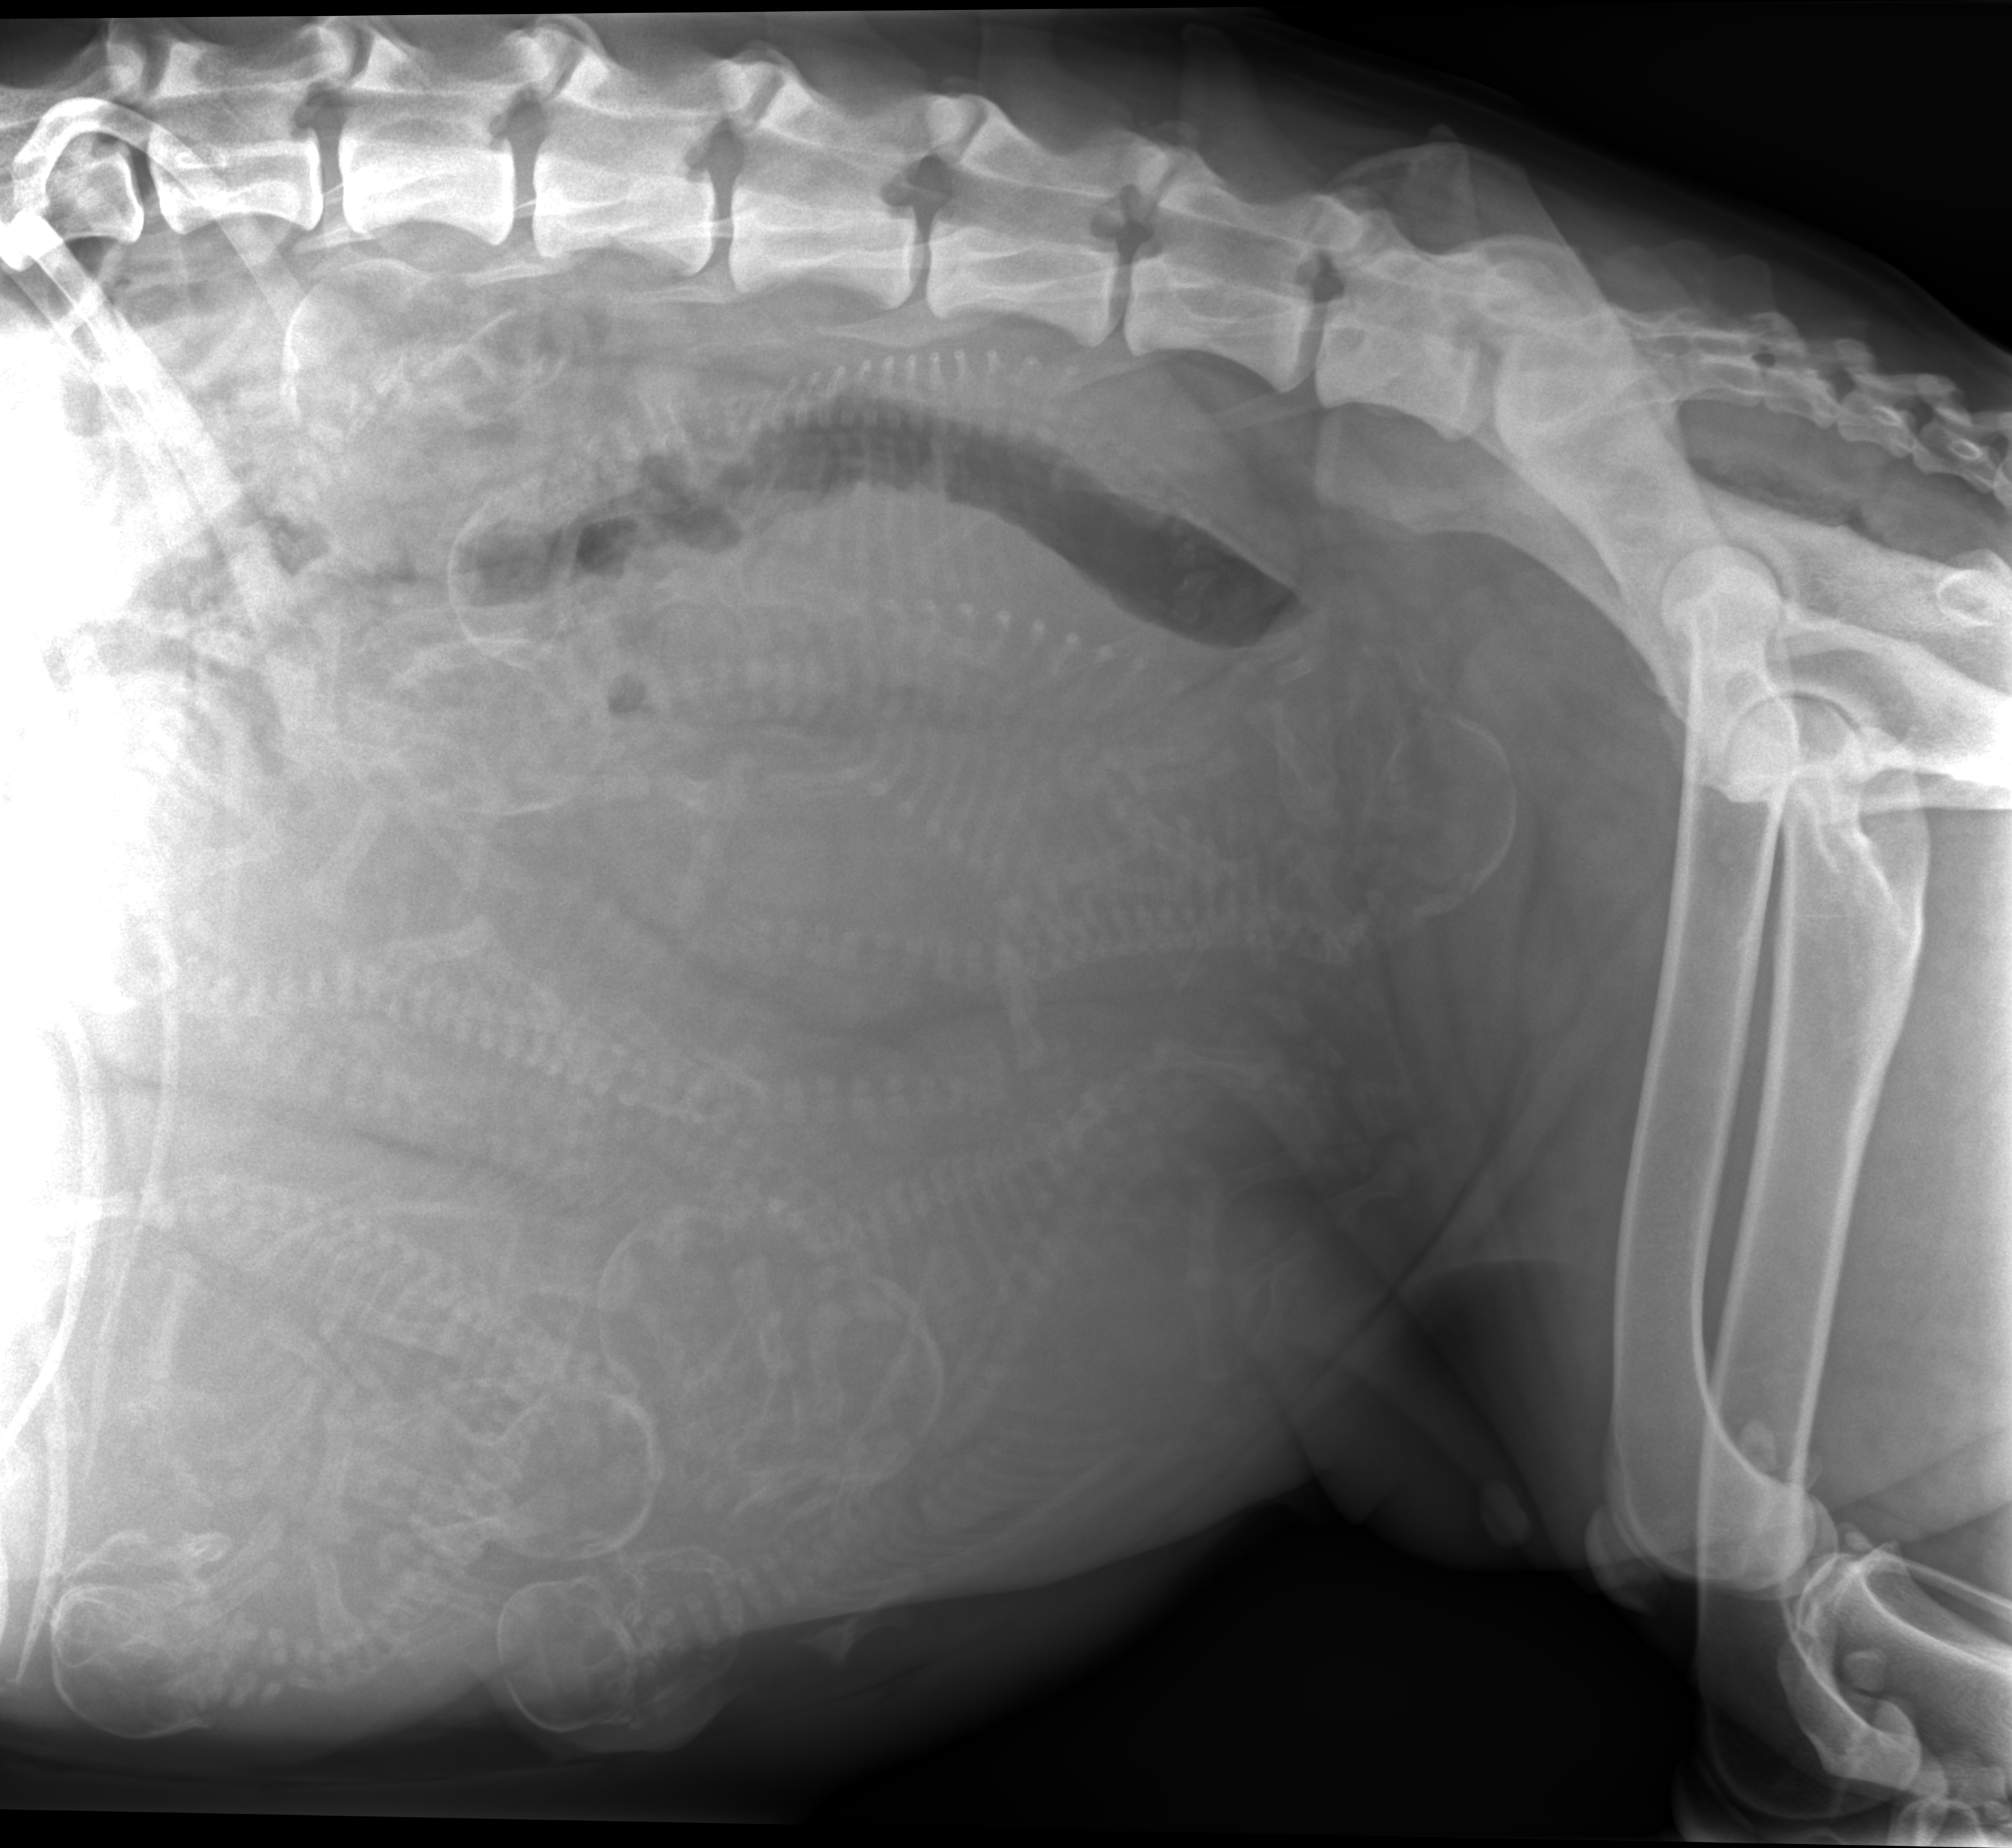

Dette blir brukshund valper fra korthåret Schæfere hvor begge har IGP3 og begge er HD/AD frie.

Både Timotei og Daisy er høydriftige hunder, veldig lærevillige og Daisy er aktiv i både lydighet (Norgesmester i LP2 for Schæferhunder i 2023) og i RIK programmet (IGP/SL/IBGH) Gode familiehunder som må trenes og som elsker å trene. Daisy er avlskåret etter Tysk mønster. Timotei er avlskåret både i Tsjekkia og i Danmark. Termin medio januar. Leveringsklare ved 8 ukers alder. Kennel Hundhamaren avler etter Norsk Schæferhundklubb sine retningslinjer og alle valper blir levert registrert i Norsk Kennelklubb (NKK), vaksinert, chippet, 2-3 ormekurer og helseattest fra veterinær.